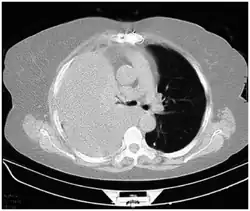

Computed tomography (CT or CAT) scans may be useful for diagnosing retained hemothorax as this form of imaging can detect much smaller amounts of fluid than a plain chest X-ray. However, CT is less used as a primary means of diagnosis within the trauma setting, as these scans require a critically ill person to be transported to a scanner, are slower, and require the subject to remain supine.[23][26]

Ultrasound scan of the chest showing a left-sided hemothorax -

CT scan of the chest showing a hemothorax caused by warfarin use -